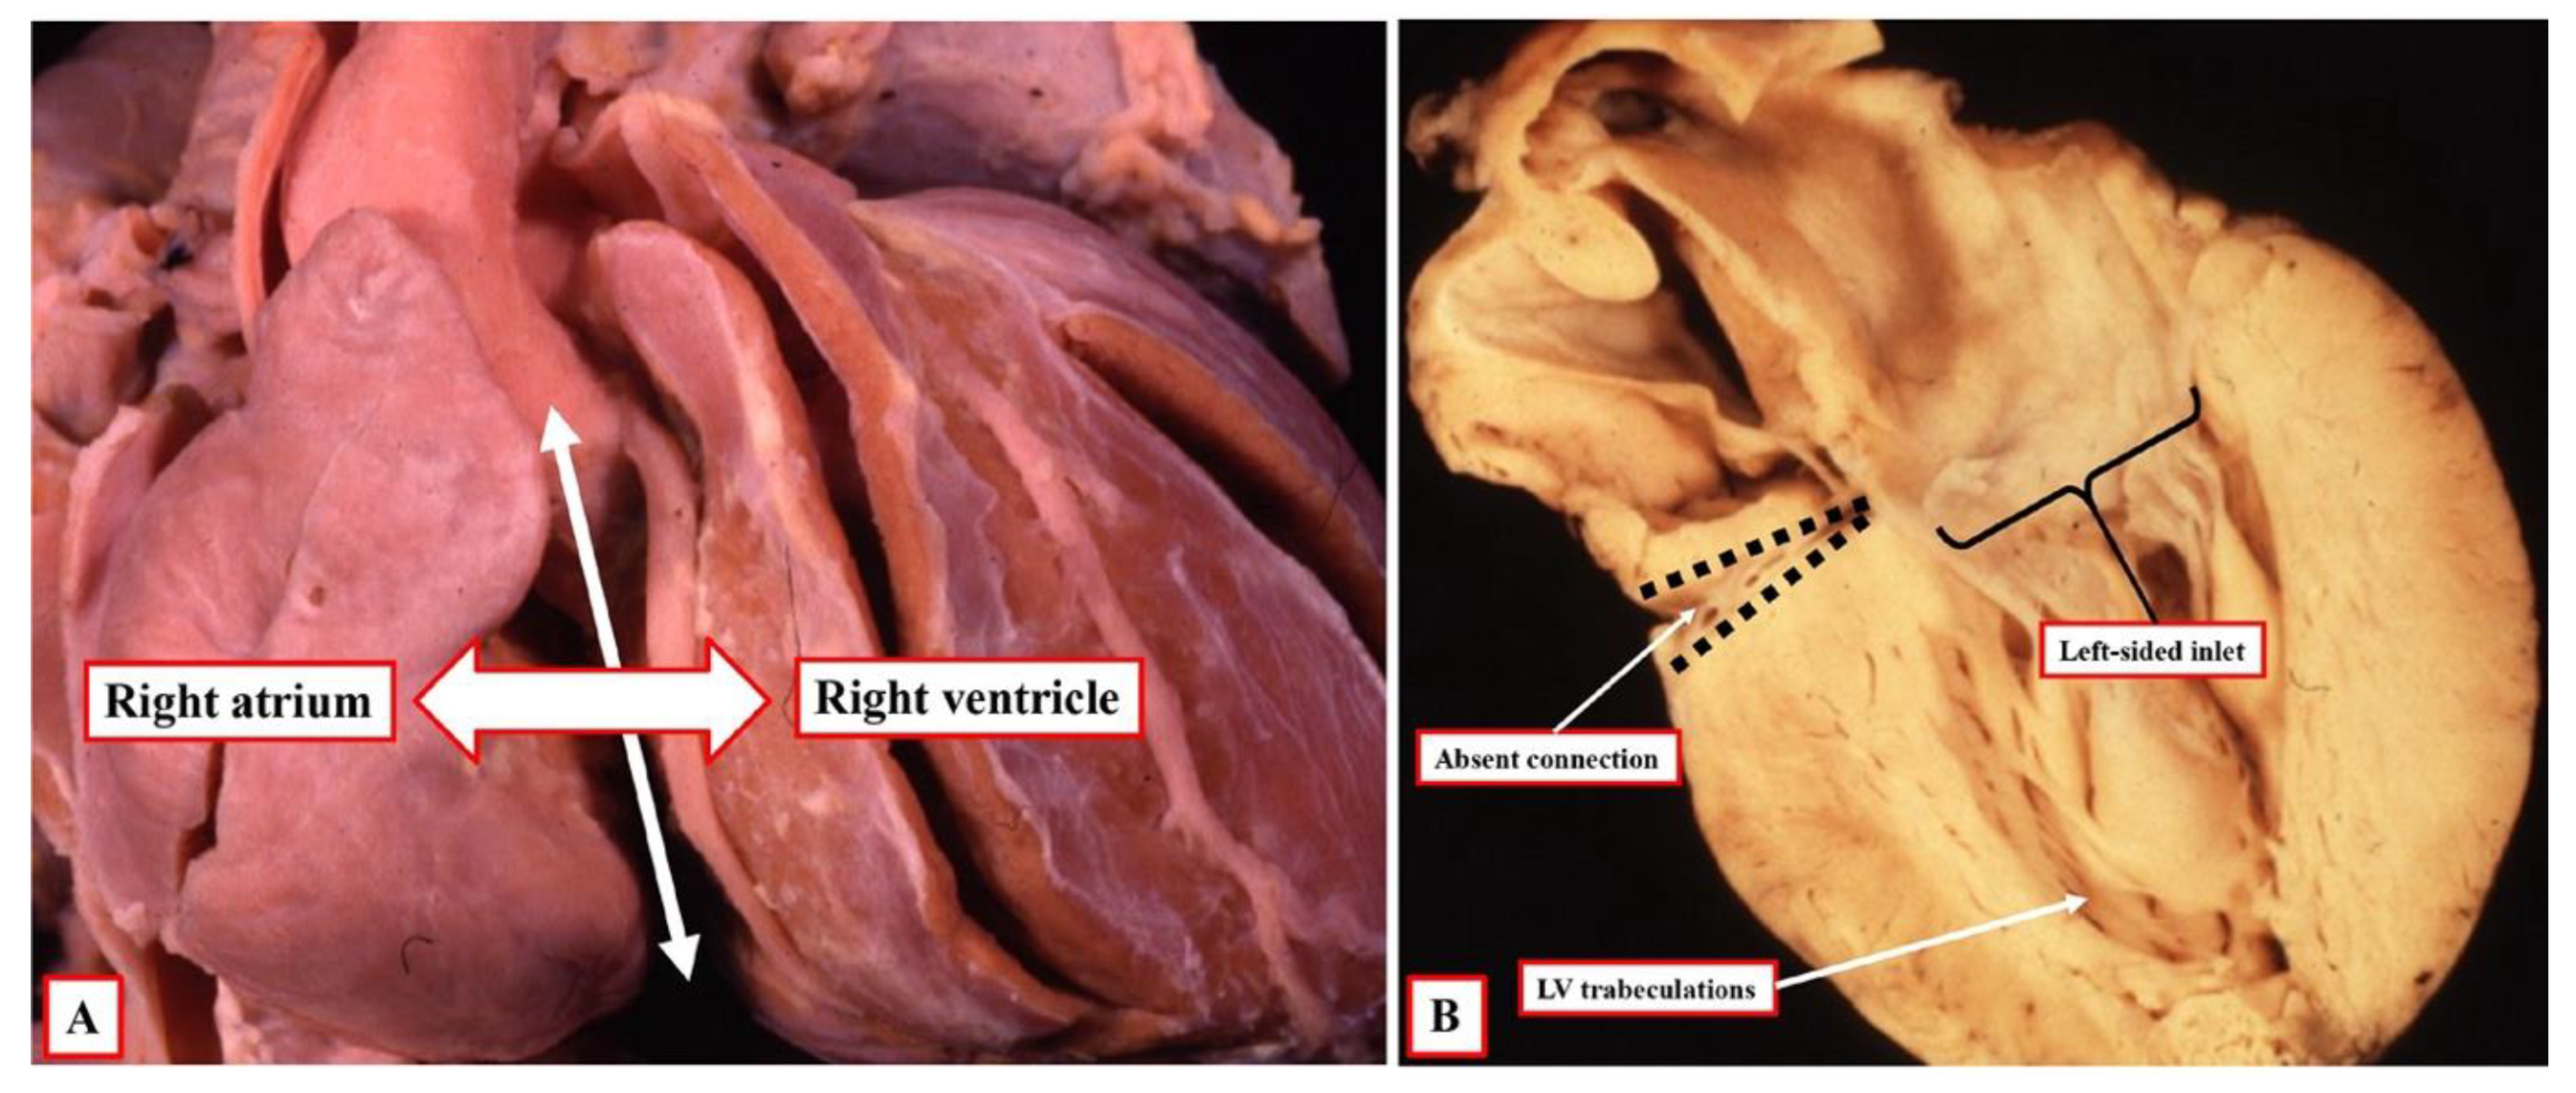

9]. This has been an unfortunate development since, in the setting of the commonest variant of tricuspid atresia, the cavity of the right atrium can be aligned with the cavity of the incomplete right ventricle, but in the absence of any direct connection between the cavities of the right atrium and right ventricle (

Figure 1). Alignments, therefore, cannot be considered to describe the same features as connections. It is possible, however, that an understanding of the role of ventricular topology can now serve to bridge the schism that has developed between the segmental and sequential segmental approaches. As already emphasised, nonetheless, the initial misinterpretation has been corrected by those promoting the sequential approach. This is because the system now avoids using the terms “atrioventricular concordance” and “discordance”. Instead, when accounting for specific connections across the atrioventricular junctions, those using the sequential approach describe concordant as opposed to discordant atrioventricular connections [

The arrangement at the early stage is pertinent to the commonest variant of tricuspid atresia, which is shown in

Figure 1. Since the right side of the atrioventricular orifice opens into the developing left ventricle, the developing right ventricle lacks a direct atrial input (

Figure 2B). In consequence, the developing right ventricle, at this early stage, is incomplete, possessing only apical and outlet components. The left ventricle, in turn, possesses only inlet and apical components. At this early stage, therefore, it is not possible to determine with precision the topological arrangement of the ventricle mass. The relationship of the incomplete right ventricle to the dominant left ventricle could be changed simply by rotating the heart itself.

At the initial stage, however, as also explained, the developing right ventricle lacks its inlet component. It is not possible, therefore, to establish its topology with certainty since it is not possible to anchor the thumb. This remains a problem when seeking to establish topology in postnatal hearts with univentricular atrioventricular connection to a dominant left ventricle, such as double inlet left ventricle or the commonest variant of tricuspid atresia. In most instances, nonetheless, it is possible to infer the likely ventricular topology according to the location of the incomplete ventricle. Almost without exception in these settings, the incomplete right ventricle is carried on the shoulder of the dominant left ventricle. When there is usual atrial arrangement, therefore, a right-sided and anterior location of the incomplete right ventricle can be taken as evidence of right-handed topology, for example, in the heart with tricuspid atresia, as shown in

Figure 1A.